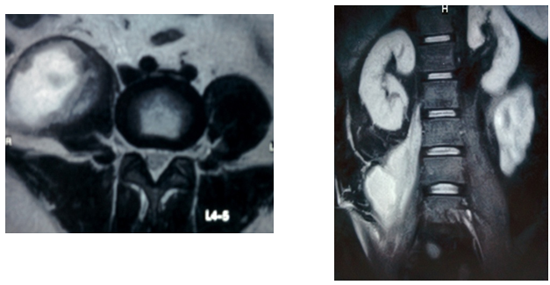

Investigations: Hemoglobin, 7 g/dL; WBC count, 12,000/µL (neutrophils 89%); erythrocyte sedimentation rate (ESR), 50 mm/h; serum creatinine, 3.2 mg/dL; serum bilirubin, 4.2 mg/dL; hepatitis E antigen, positive; 2D echocardiography, 40% ejection fraction with basal hypokinesia; X-ray of lumbosacral spine showed reduced disc space between the 12th dorsal and 1st lumbar vertebrae and also the 3rd and 4th lumbar vertebrae with increased diameter of psoas shadow seen on the left side; magnetic resonance imaging (MRI) shows a collection of approximately 15×6.6 cm in the left psoas muscle extending to the left iliacus muscle, epidural collection at the L1 vertebra compressing the thecal sac, and marrow hyperintense signal from T12 to S1 vertebrae with destruction of intervening disc space between T12–L1 and L3–L4 vertebrae (see Fig. 1).

Fig. 1: Magnetic resonance imaging scans showing iliopsoas abscess with lumbar vertebrae involvement.

A 31-year-old man presented with pain in the abdomen for the past 1.5 months and a high-grade fever for past 10 days. Renal calculus was diagnosed and appropriate treatment was given. However, the symptoms did not resolve and MRI of the lumbar spine was done. MRI showed a right-sided iliopsoas abscess measuring 3.4×4.1×7.4 cm (see Fig. 1). Computed tomography (CT)-guided biopsy analyses identified Escherichia coli and Streptococcus spp. The patient was referred to our institute at this stage for formal open drainage of the abscess.

Fig. 1: Magnetic resonance imaging scans showing a right-sided iliopsoas abscess.